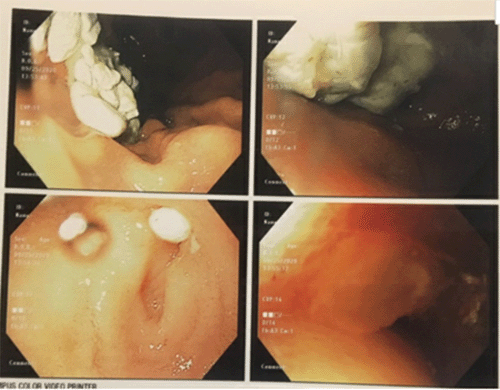

An esophagogastroduodenoscopy (EGD) showed smooth extrinsic compression with severe narrowing of the duodenal lumen at the junction of the bulb at the second portion of the duodenum (Figure 3).

Figure 3. Esophagogastroduodenoscopy (EGD). Published with Permission

Image reveals smooth extrinsic compression with severe narrowing of duodenal lumen at junction of bulb and second portion

The scope could not pass through the narrowed lumen, and the ampulla of Vater was not identified prior to the stenosis, further confirming the compression at the second portion. EGD also noted retained food in the stomach, although the patient's last solid meal was 23 hours prior (Figure 4).

Figure 4. Intubation into Stomach. Published with Permission

Image depicting retained food in stomach. Patient's last solid meal was 23 hours prior